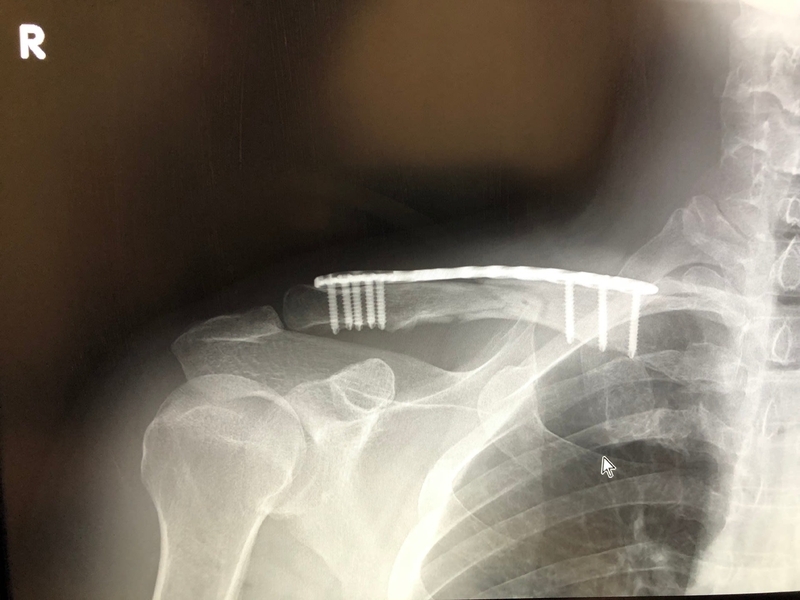

術後35日目。超音波骨折治療を始めてから14日目。

レントゲンに映る鎖骨は、素人の私が見てもまだ骨がくっついてないことがわかります。